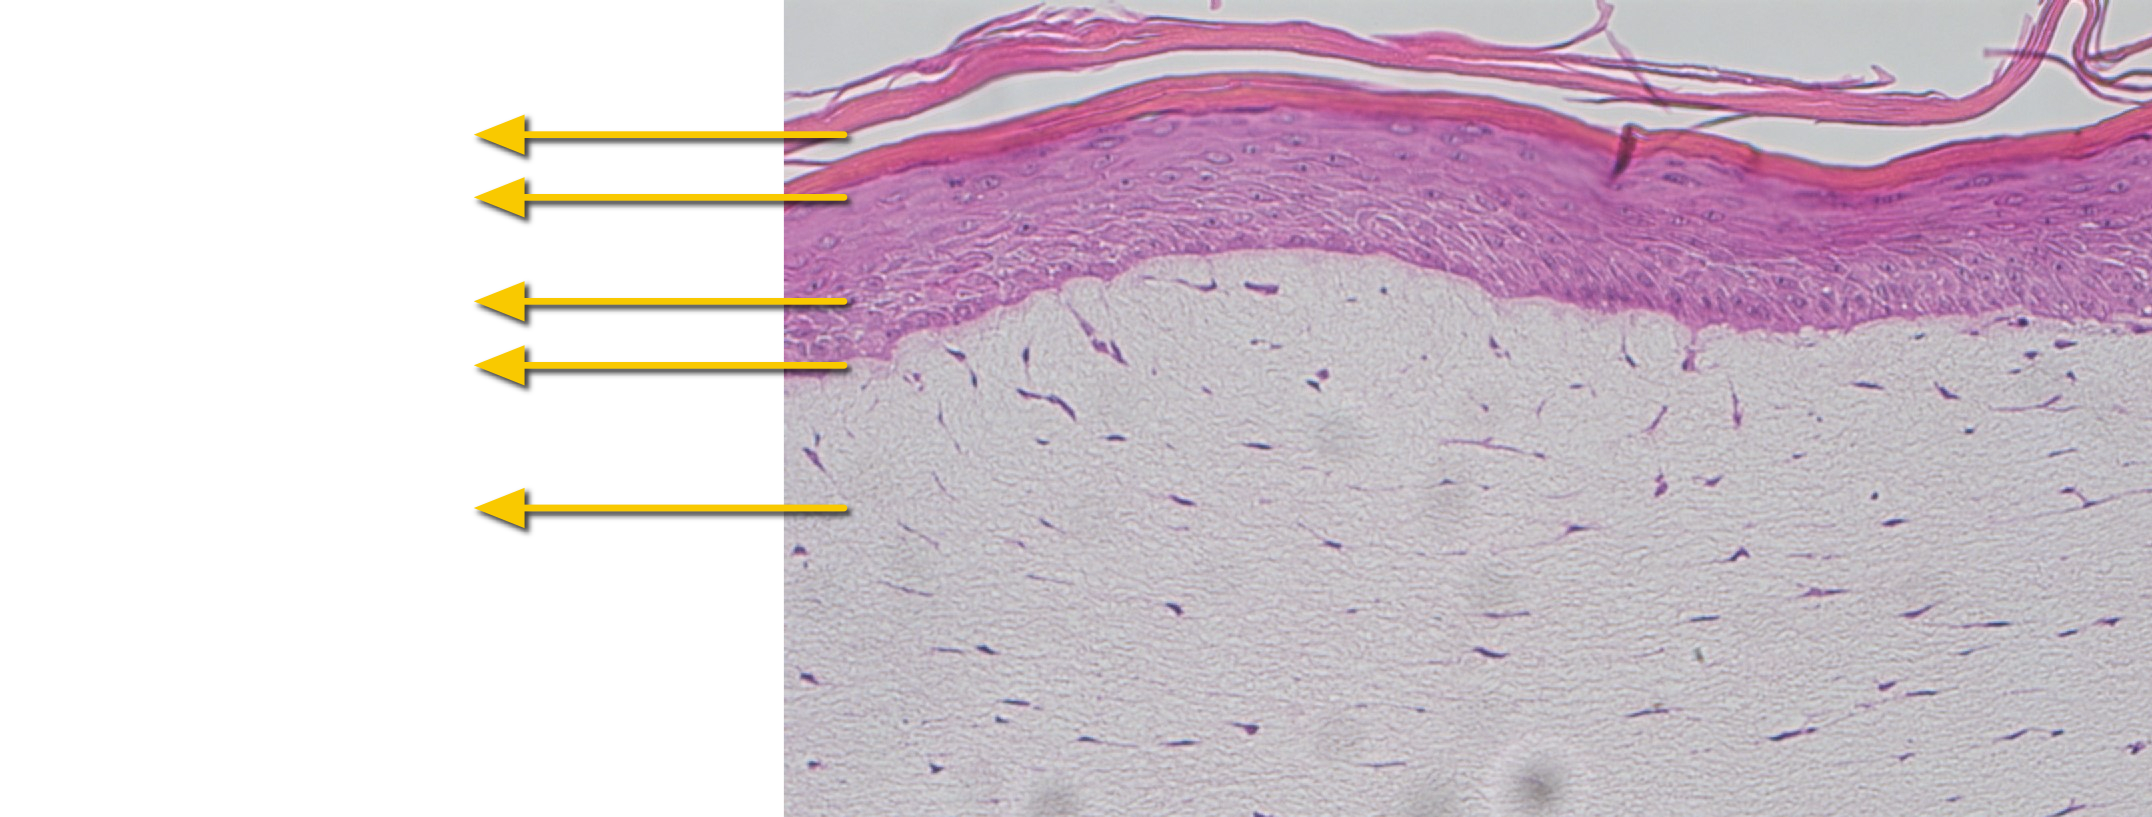

- Basic research in skin physiology and biochemistry

- Dermatological clinical research

- Skin penetration studies (barrier property)